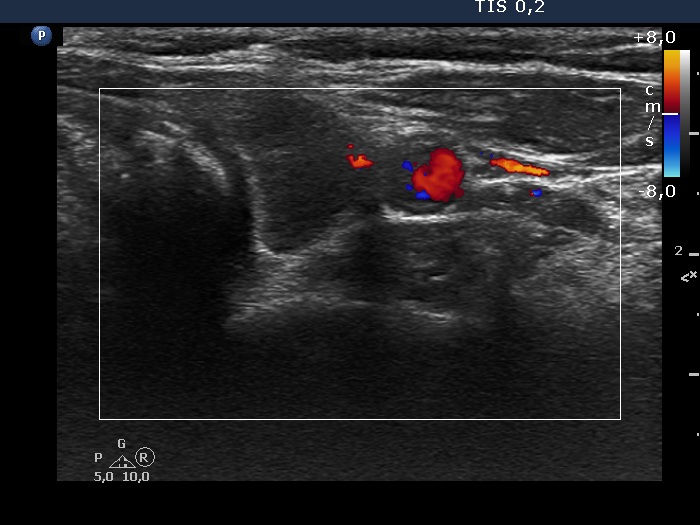

First examination (first, third and fifth rows of images):

Ultrasonography. The thyroid was echonormal and contained multiple inhomogeneous, partly blurred hypoechogenic and moderately hypoechogenic discrete lesions. Multiple lymph nodes were found on both sides of the neck.